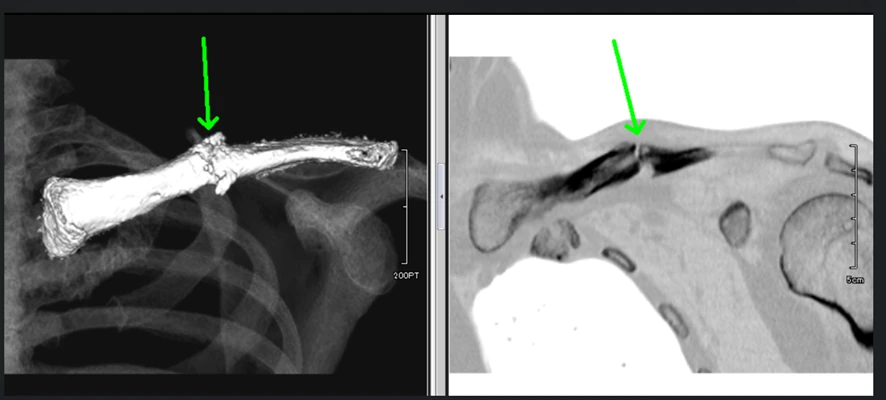

① 鎖骨骨折のCT画像

※矢印部で骨癒合が認められず偽関節になっています。